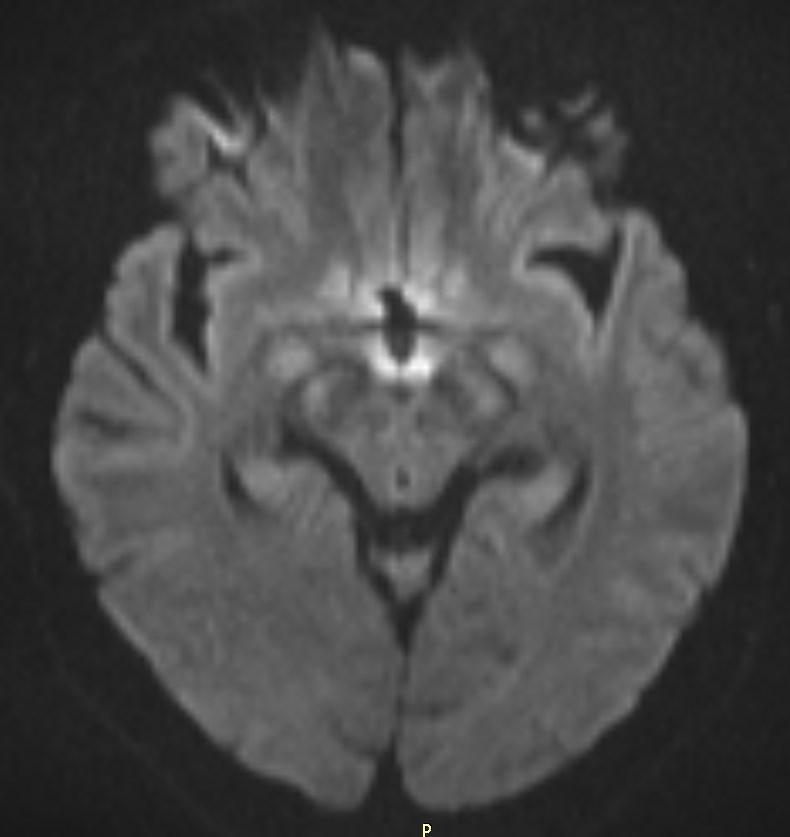

MRI images revealed hyperintensities in the periaqueductal region and the medial thalami.

T2/FLAIR: symmetrically increased signal intensity in the mamillary bodies, dorsomedial thalami, tectal plate, periaqueductal area, and around the third ventricle.